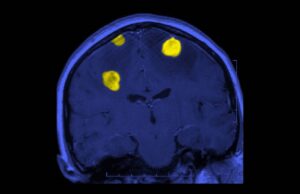

Dan esperanza a pacientes con tumores cerebrales

Los tumores cerebrales ocupan el lugar 19 entre todas las neoplasias, y el 10 entre las más letales. A nivel mundial, cada año se...